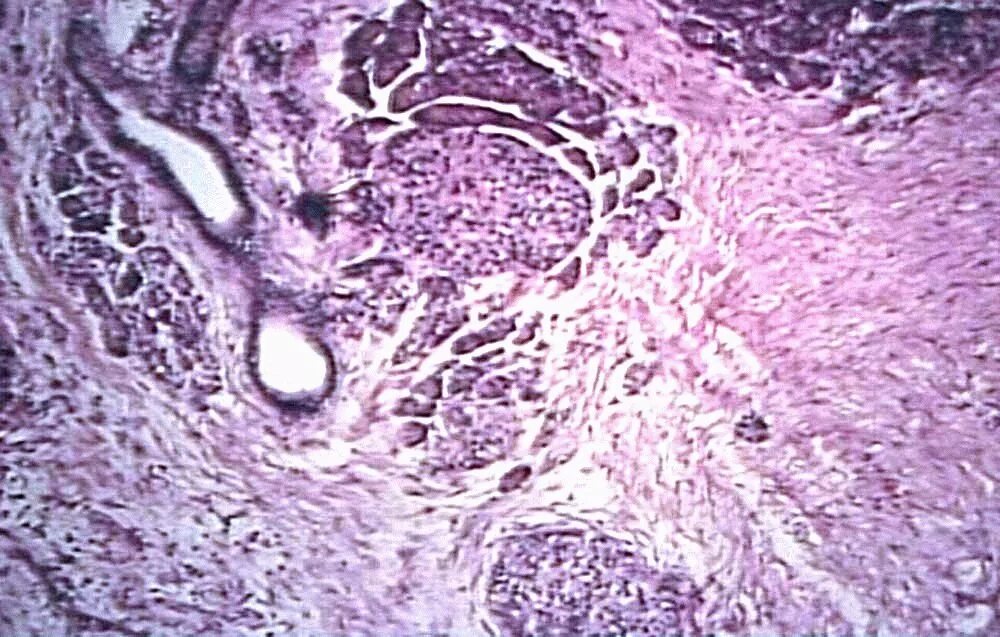

Гистология печени и поджелудочной железы